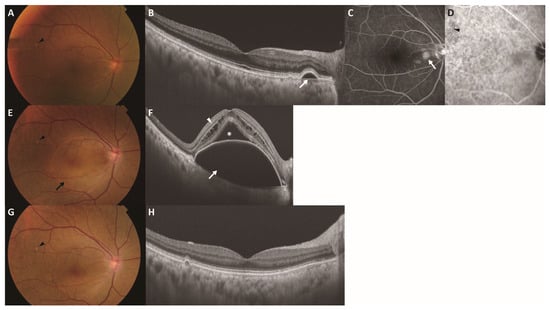

Five-Year Changes in Pachydrusen with Late-Phase Hyperfluorescence on Indocyanine Green Angiography

by Hiroyuki Kamao, Katsutoshi Goto, Kenichi Mizukawa, Ryutaro Hiraki, Atsushi Miki and Shuhei Kimura

J. Clin. Med. 2026, 15(8), 2836; https://doi.org/10.3390/jcm15082836 (registering DOI) - 9 Apr 2026

Background/Objectives: Pachydrusen are a drusen subtype associated with the pachychoroid disease spectrum; however, their long-term natural history and pathophysiological significance remain unclear. We investigated 5-year morphological and topographic changes in pachydrusen using diagnostic criteria incorporating late-phase indocyanine green angiography (ICGA) hyperfluorescence. Methods: This retrospective observational study included fellow eyes with pachydrusen from patients with unilateral neovascular age-related macular degeneration. Pachydrusen were defined as sub-retinal pigment epithelium (RPE) deposits ≥ 125 µm in size with corresponding hyperfluorescence on late-phase ICGA. Lesion number, size, and spatial distribution (ETDRS grid and quadrant-based classification) were evaluated at baseline and 5 years. The incidence of macular neovascularization (MNV) and its colocalization with pachydrusen were assessed. Results: Among 57 fellow eyes with pachydrusen, incident MNV developed in 8 eyes (14.0%) during follow-up; the mean time to onset was 25.6 ± 16.3 months. No clear colocalization between pachydrusen and incident MNV was observed. Nineteen eyes completed the 5-year follow-up period. Pachydrusen were predominantly located outside the 6000 µm ETDRS grid at baseline (63.4%) and 5 years (66.3%), significantly exceeding the expected proportion based on the area ratio (p < 0.001). The lesions were most frequently observed in the superotemporal quadrant (52.6%). Over 5 years, 19.8% of the lesions increased in size, 67.2% remained stable, and 12.9% regressed; none of the regressed lesions were accompanied by RPE atrophy. Conclusions: Pachydrusen, defined as late-phase ICGA hyperfluorescence, was predominantly distributed outside the ETDRS grid with a superotemporal predilection and could increase or decrease over a 5-year follow-up period. No colocalization with MNV was observed, and no accompanying RPE atrophy after pachydrusen regression was identified, suggesting that late-phase ICGA–hyperfluorescent pachydrusen may represent a pathophysiology distinct from that of soft drusen. Full article

Show Figures

Figure 1